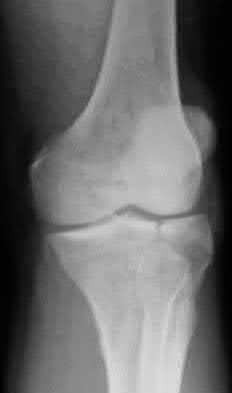

Figure A is an AP radiograph of a posterior knee dislocation. Figure B is a lateral showing the same injury.